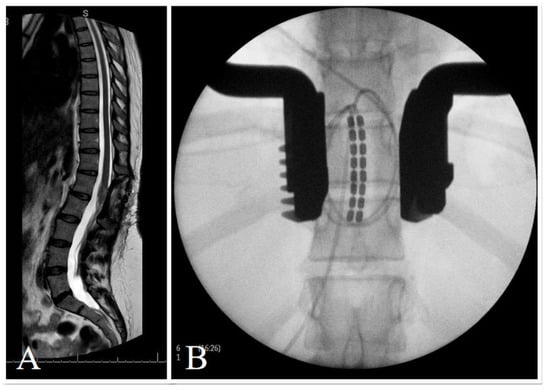

| 49 | F | Ependymoma | Retrograde paddle T9–10 | Boston (Marlborough, MA, USA)  | Microburst | T9 |

| 52 | M | Spinal stroke T3 | Paddle T9 | Abbott | BurstDR | T9–10 |